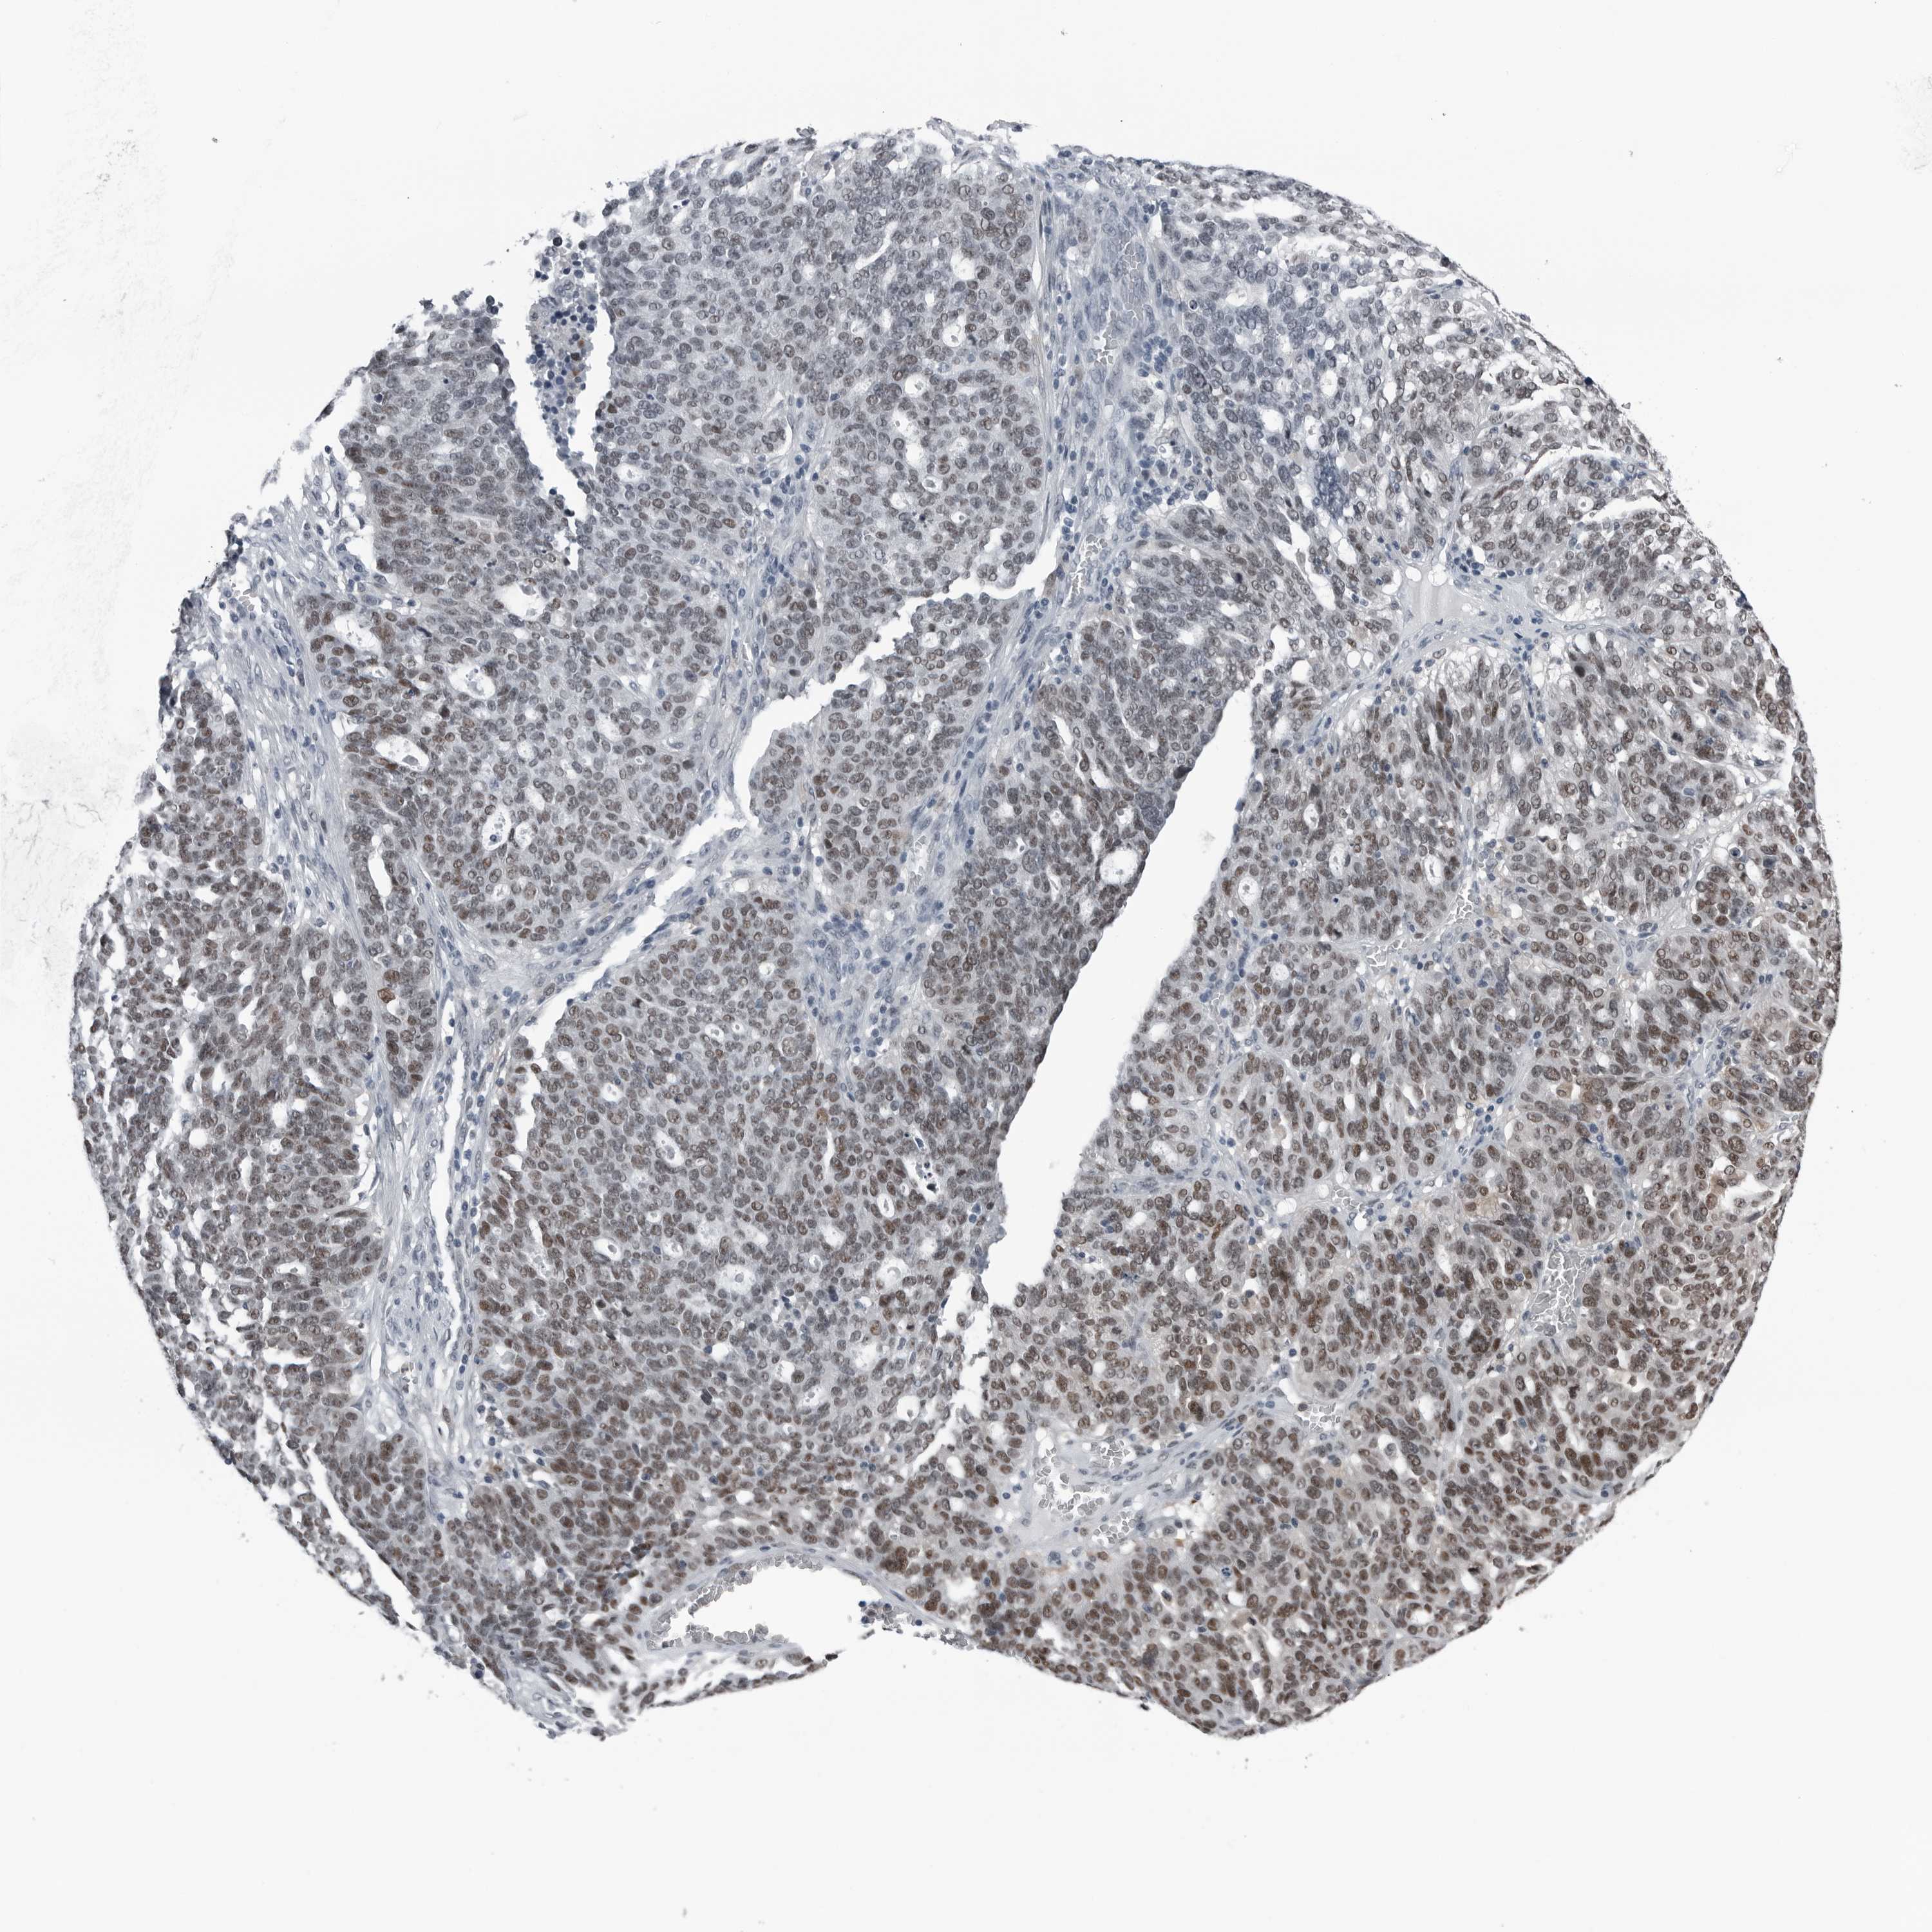

OVARIAN CANCER - Protein expressioni

A mouse-over function shows sample information and annotation data. Click on an image to view it in a full screen mode. Samples can be filtered based on level of antibody staining by selecting one or several of the following categories: high, medium, low and not detected. The assay and annotation is described here.

Note that samples used for immunohistochemistry by the Human Protein Atlas do not correspond to samples in the TCGA dataset.

Antibody stainingi

Antibody staining in the annotated cell types in the current human tissue is reported as not detected, low, medium, or high, based on conventional immunohistochemistry profiling in selected tissues. This score is based on the combination of the staining intensity and fraction of stained cells.

Each image is clickable and will lead to virtual microscopy that enables deeper exploration of all samples and also displays staining intensity scores, fraction scores and subcellular localization as well as patient and tissue information for each sample.

Antibody HPA027734

High

Medium

Low

Not detected

Cystadenocarcinoma, mucinous, NOS